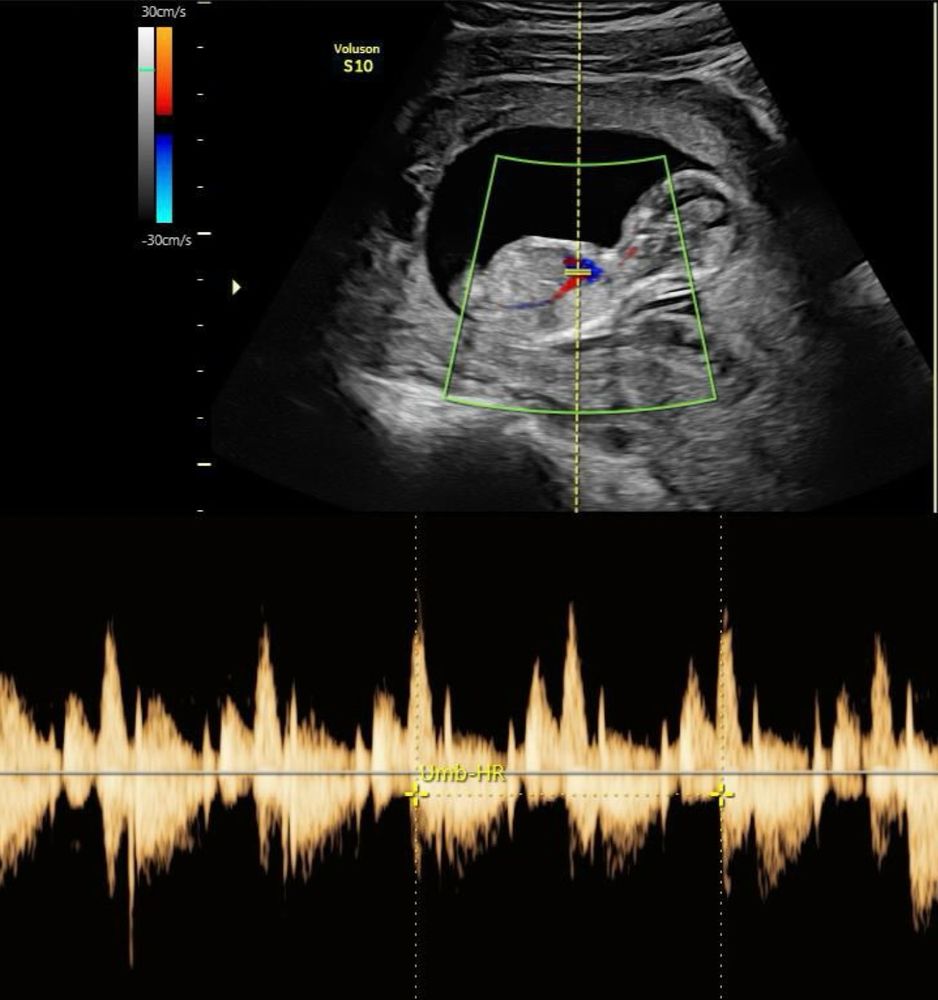

исутствовала на узи

Присутствовала на узи 118 фотографий

Диамед 24